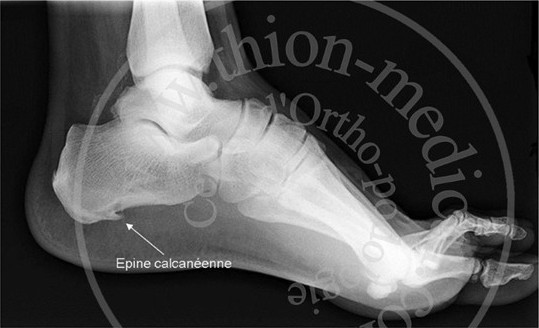

C’est une inflammation de l’aponévrose plantaire localisée au niveau de son insertion sous le calcanéum.

Elle n’est pas forcément associée à la présence d’une épine calcanéenne (Calcification inflammatoire de l’insertion de l’aponévrose plantaire sous le calcanéum).